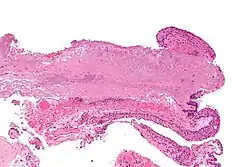

Pathology

Pterygium in the conjunctiva is characterized by elastotic degeneration of collagen (actinic elastosis[12]) and fibrovascular proliferation. It has an advancing portion called the head of the pterygium, which is connected to the main body of the pterygium by the neck. Sometimes a line of iron deposition can be seen adjacent to the head of the pterygium called Stocker's line. The location of the line can give an indication of the pattern of growth.